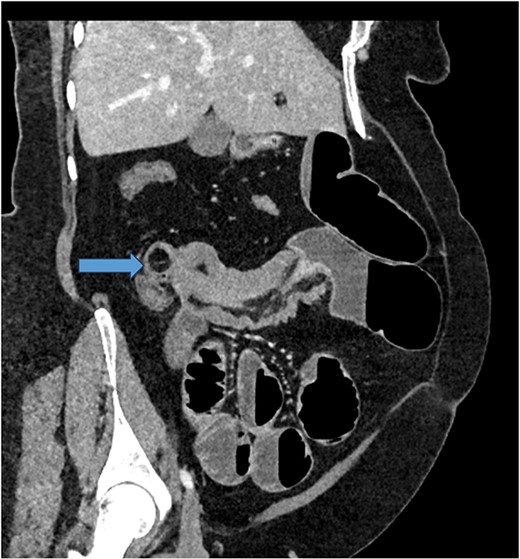

Given her abdominal symptoms and signs, she was subjected to an abdominal X-ray (Fig. 1), which showed multiple distended loops of the small bowel, and a chest X-ray, which showed left basal atelectasis. A working diagnosis of SBO was made. She was put nil by mouth. A nasogastric tube and a urinary catheter were inserted. After initial resuscitation, she was subjected to CTAP with contrast. The findings of the CTAP were in keeping with acute distal SBO secondary to an ileo-ileal intussusception. No obvious mucosal mass was stated in the initial report (Figs 2 and 3).

CT Abdomen: MPR reconstruction of the plane of intussusception showing a distal lipoma and proximal start of intussusception.